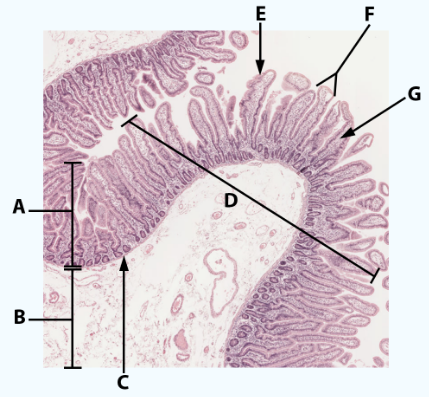

A

Mucosa: simple columnar epithelium with microvilli

B

Submucosa

C

muscularis mucosa

Area

Small intestine

E

simple columnar epithelium with goblet cells and microvilli

F

Villi

G

Lamina propria